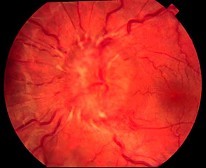

患者,女性,35岁,双眼视力突然下降,同时伴有头痛、耳鸣、听力下降、毛发变白,查见右眼视力0.1,左眼0.08,角膜后KP阳性,前方闪辉阳性,眼底检查如图,对该病描述正确的是()

-